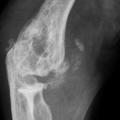

Le patient non traité par hypo-uricémiant peut développer une goutte polyarticulaire chronique caractérisée par des articulations douloureuses et gonflées en permanence, l’apparition de tophus (fig. 1) voire d’une arthropathie destructrice (fig. 2 et 3), et des manifestations rénales (lithiase rénale, le plus souvent uratique, néphropathie interstitielle …).

La forme pseudorhumatoïde est rare (5 %), simulant une polyarthrite rhumatoïde (diagnostic différentiel), avec parfois des signes systémiques d’inflammation (élévation de la vitesse de sédimentation et de la CRP). Le diagnostic repose sur la mise en évidence des cristaux de PPC. La radio peut mettre en évidence des calcifications des cartilages articulaires (fig. 6) et des fibrocartilages (fig. 7, 8, 9 et 10). L’échographie (plus sensible) peut mettre en évidence des dépôts de PPC, qui apparaissent comme une fine bande hyperéchogène au sein des cartilages hyalins et comme des points scintillants dans les fibrocartilages ou dans la membrane synoviale. Dans l’arthrite chronique à PPC, lespossibilités thérapeutiques sont, par ordre de préférence : colchicine (de 0,5 à 1 mg/j), petites doses de cortisone, parfois les AINS per os (mais leur prescription est souvent limitée par les comorbidités chez les patients âgés), méthotrexate et l’hydroxychloroquine. Il n’y a pas aujourd’hui de traitement « de fond », mais des molécules sont à l’étude.